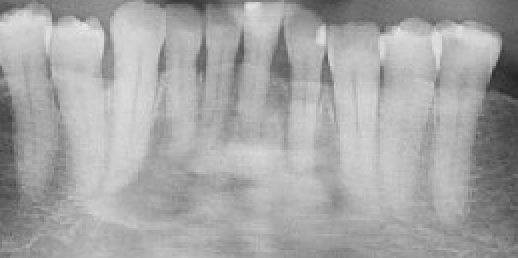

COD is classified into three subtypes, periapical, focal, and florid (Figure 1), depending on location and distribution within the jaw. It occurs most commonly in middle-aged women and is more frequent in individuals of African or Asian descent [1, 2].

As COD matures, the lesions progress from a radiolucent (soft tissue) stage to a mixed stage and, finally, to a radiopaque, sclerotic stage. In the mature stage, the bone becomes poorly vascularized, which significantly affects its ability to heal and resist infection [3].

Figure 1. Part of a panoramic radiograph showing cemento-osseous dysplasia in the mandible with the mixed radiopaque and radiolucency diffuse appearance periapical to teeth.